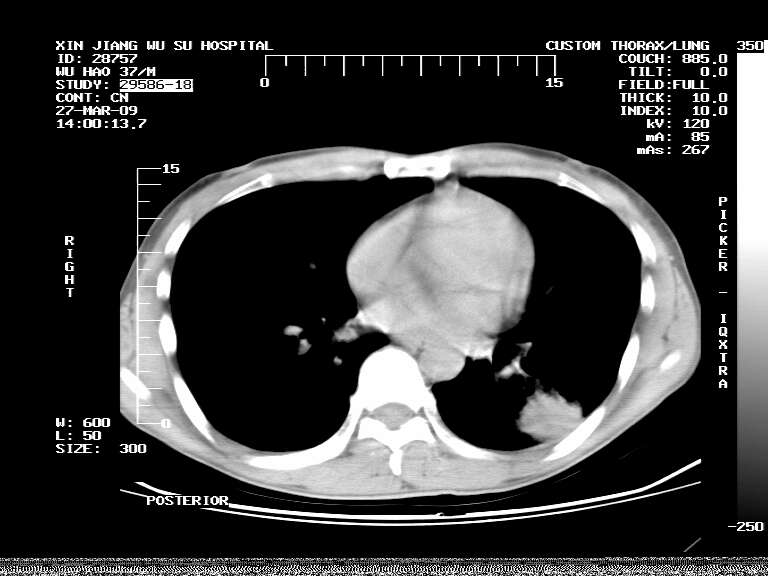

男,37岁,体检胸透发现阴影。

患者体检发现 无症状 左肺下叶占位,边缘模糊,可见血管聚束、分叶、胸膜牵拉,增强呈不均匀性强化。 首先考虑左肺下叶周围型肺癌,建议穿刺活检。

左肺下叶见一结节病变,边缘欠清不光滑,与胸膜粘连且胸膜局限性增厚,注药后呈环形强化,动脉期壁呈明显点环状强化,静脉期壁强化减低,中心密度低无强化,灶周无明显的卫星灶和水肿区(晕征)---考虑周围性肺癌,不除外感染性病变,建议穿刺活检。

左肺下叶软组织病灶,密度较高,内见点状钙化,其周围见子灶,邻近胸膜扁平样增厚.c+病灶强化明显,中心强化弱.诊断:左肺下叶结核瘤.

左肺下叶大片实变影,内靠胸膜见不规则更高密度结节灶,边缘强化,相邻胸膜增厚,胸膜下脂肪线存在。考虑炎症,结核可能。